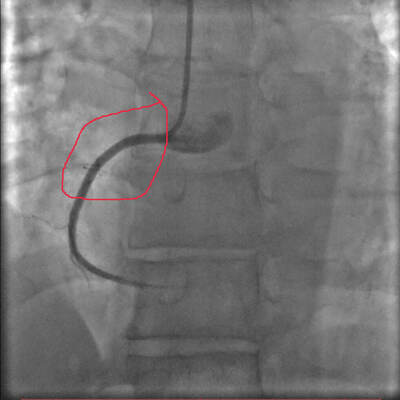

И что же там?? На коронарографии? Для краткости пару проекций (видео)

Скобками показан пораженный участком правой коронарной артерии (расслоение сосуда, вследствие надрыва стенки). Правая артерия часто вторая по значимости после передней.